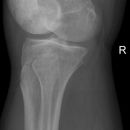

Tunnelaufnahme nach Frik

Dient der Beurteilung der Fossa und der Eminentia intercondylaris, sowie der Femurkondylen. Zudem hilfreich bei der Diagnostik der Osteochondrosis dissecans (2) -> Prädilektionsstelle: laterale Anteil der medialen Femurkondyle.